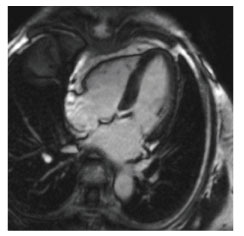

当院のMRI画像集